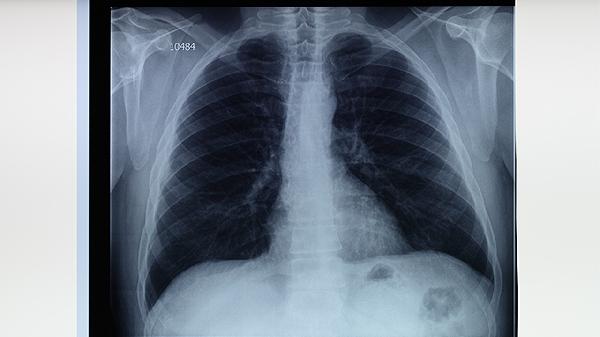

非活动性肺结核CT的表现

非活动性肺结核在CT上主要表现为纤维钙化灶、胸膜增厚、支气管扩张等特征性改变。影像学表现主要有陈旧性结核结节、肺门淋巴结钙化、局限性胸膜粘连、肺叶体积缩小、支气管扭曲变形五种典型征象。